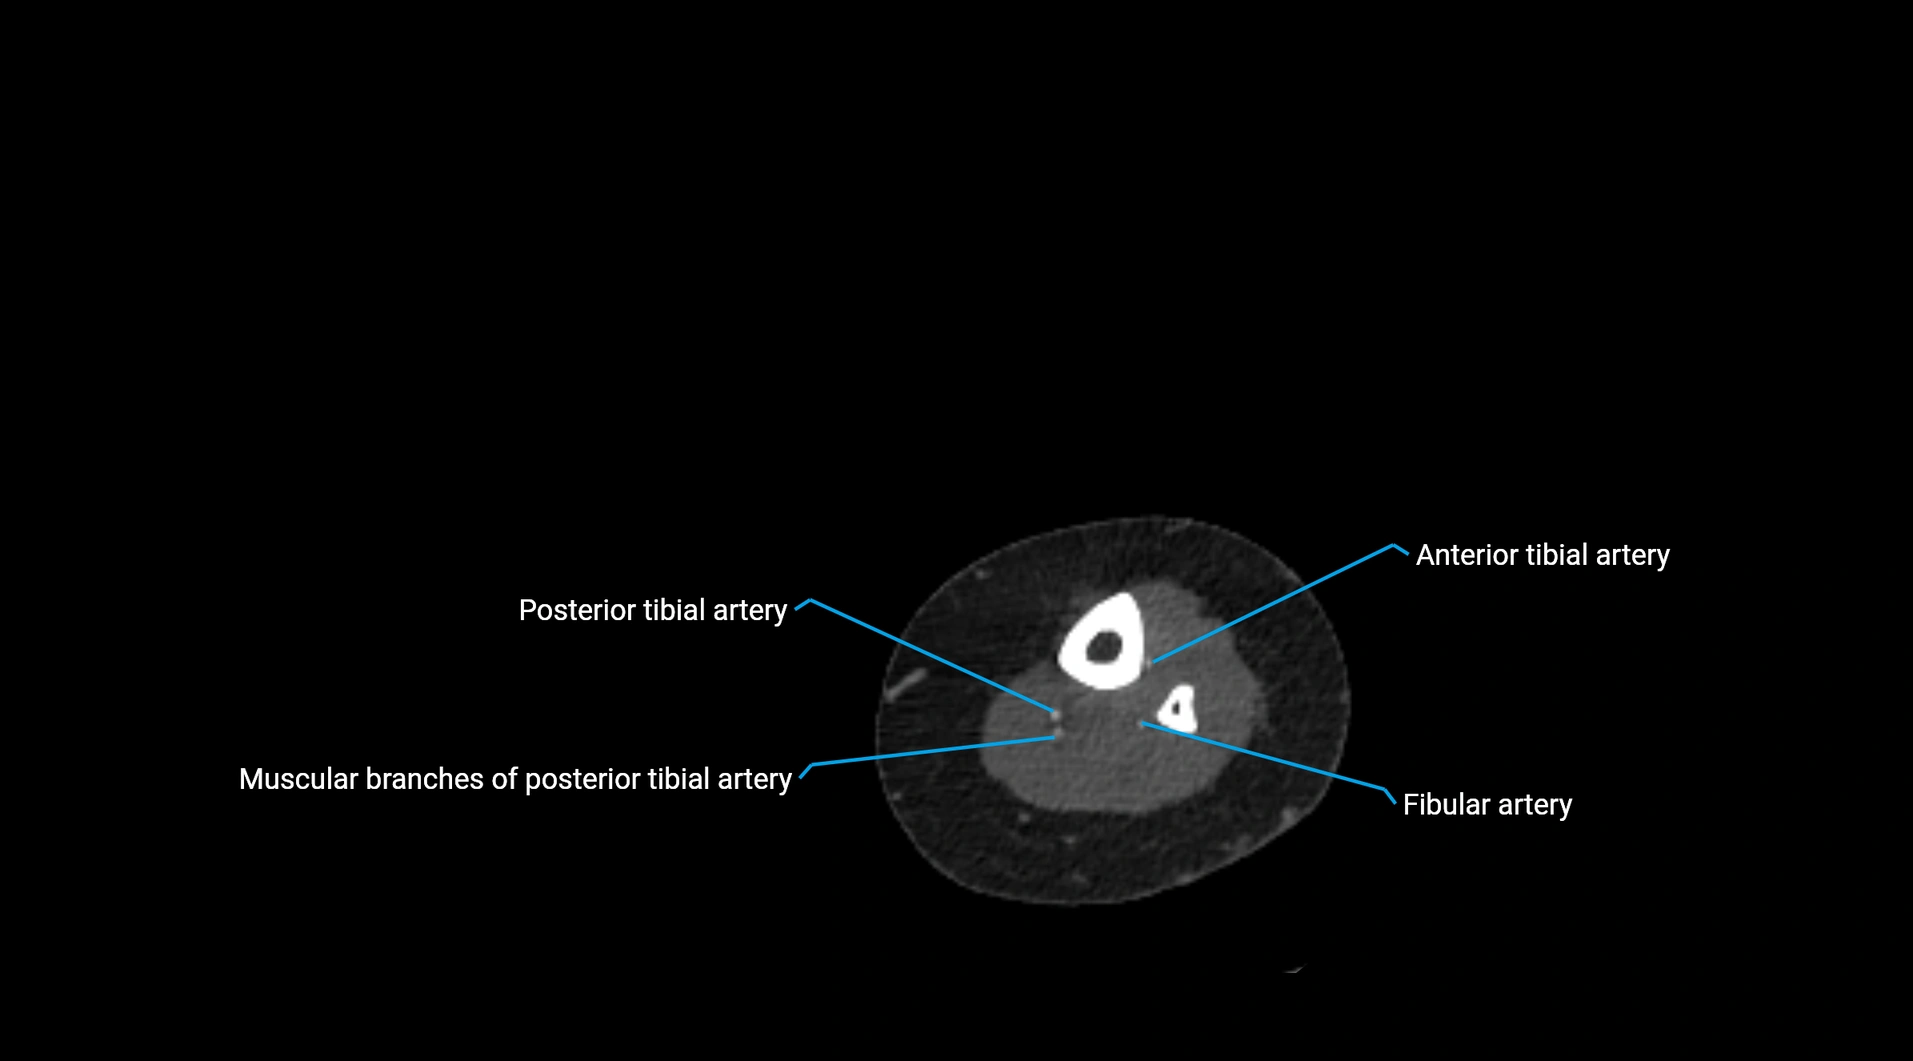

CT images

image

Contrast-enhanced CT (CTA):

• Gold standard for abdominal aortic imaging

• Provides excellent detail of lumen, wall, aneurysm, thrombus, and branch vessels

• Multiplanar and 3D reconstructions help in aneurysm measurement, stent graft planning, and dissection evaluation